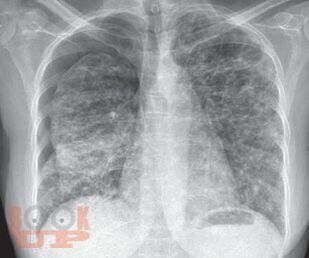

First textbook about pleural disease written and edited by Indian authors. First pleural textbook which has contributions from multiple authors. Textbook of pleural disease which has been authored by multiple specialtiesa unique feature where each chapter has been written by the concerned specialists, e.g., pleural disease in kidney disease by nephrologist, hepatic hydrothorax by hepatologist, and pleural disease in gynecological disorder by gynecologist. Every aspect of pleura from embryology, anatomy, physiology, and radiological diagnosis has been covered in detail. Role of ultrasonography in pleura, which is now a vital tool for point-of-care management has been described in detail. High-quality pleural imaging and its highlights are shown in concerned chapters Pathophysiologic basis of pleural diseases has been discussed with each specific disease. Concise algorithm summarizing disease management has been clearly depicted. Updated treatment as per recent guidelines has been incorporated. The topics in pleural diseases have been written by eminent chest physicians all over India. A special chapter describes pleural diseases in COVID, in the post pandemic era. Being a Lung Transplant center, a special chapter on overview on pleura issues in lung transplant has been elaborated.